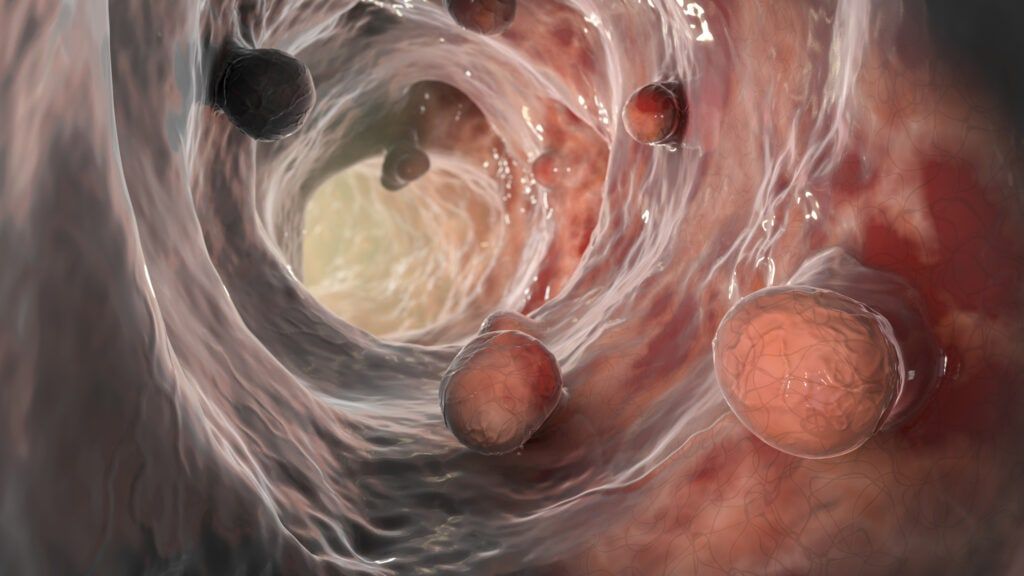

Well, a huge breakthrough has been reached for those diagnosed with colorectal cancer, found in the colon, or the rectum.